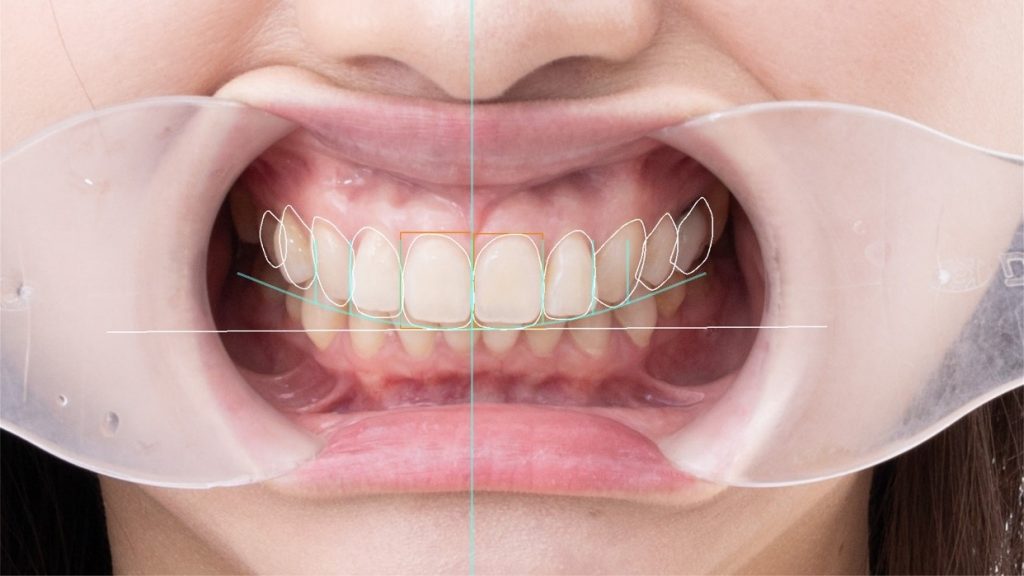

好看的笑容牽涉到口鼻、齒型與臉部間比例,微笑曲線設計即應運而生:先進行多角度的數位口腔掃描與臉部攝影,再透過電腦比對與模擬,即能在治療前預見完成的樣子,最後裝上陶瓷貼片或全瓷冠,渾然天成又獨一無二的微笑曲線即誕生!